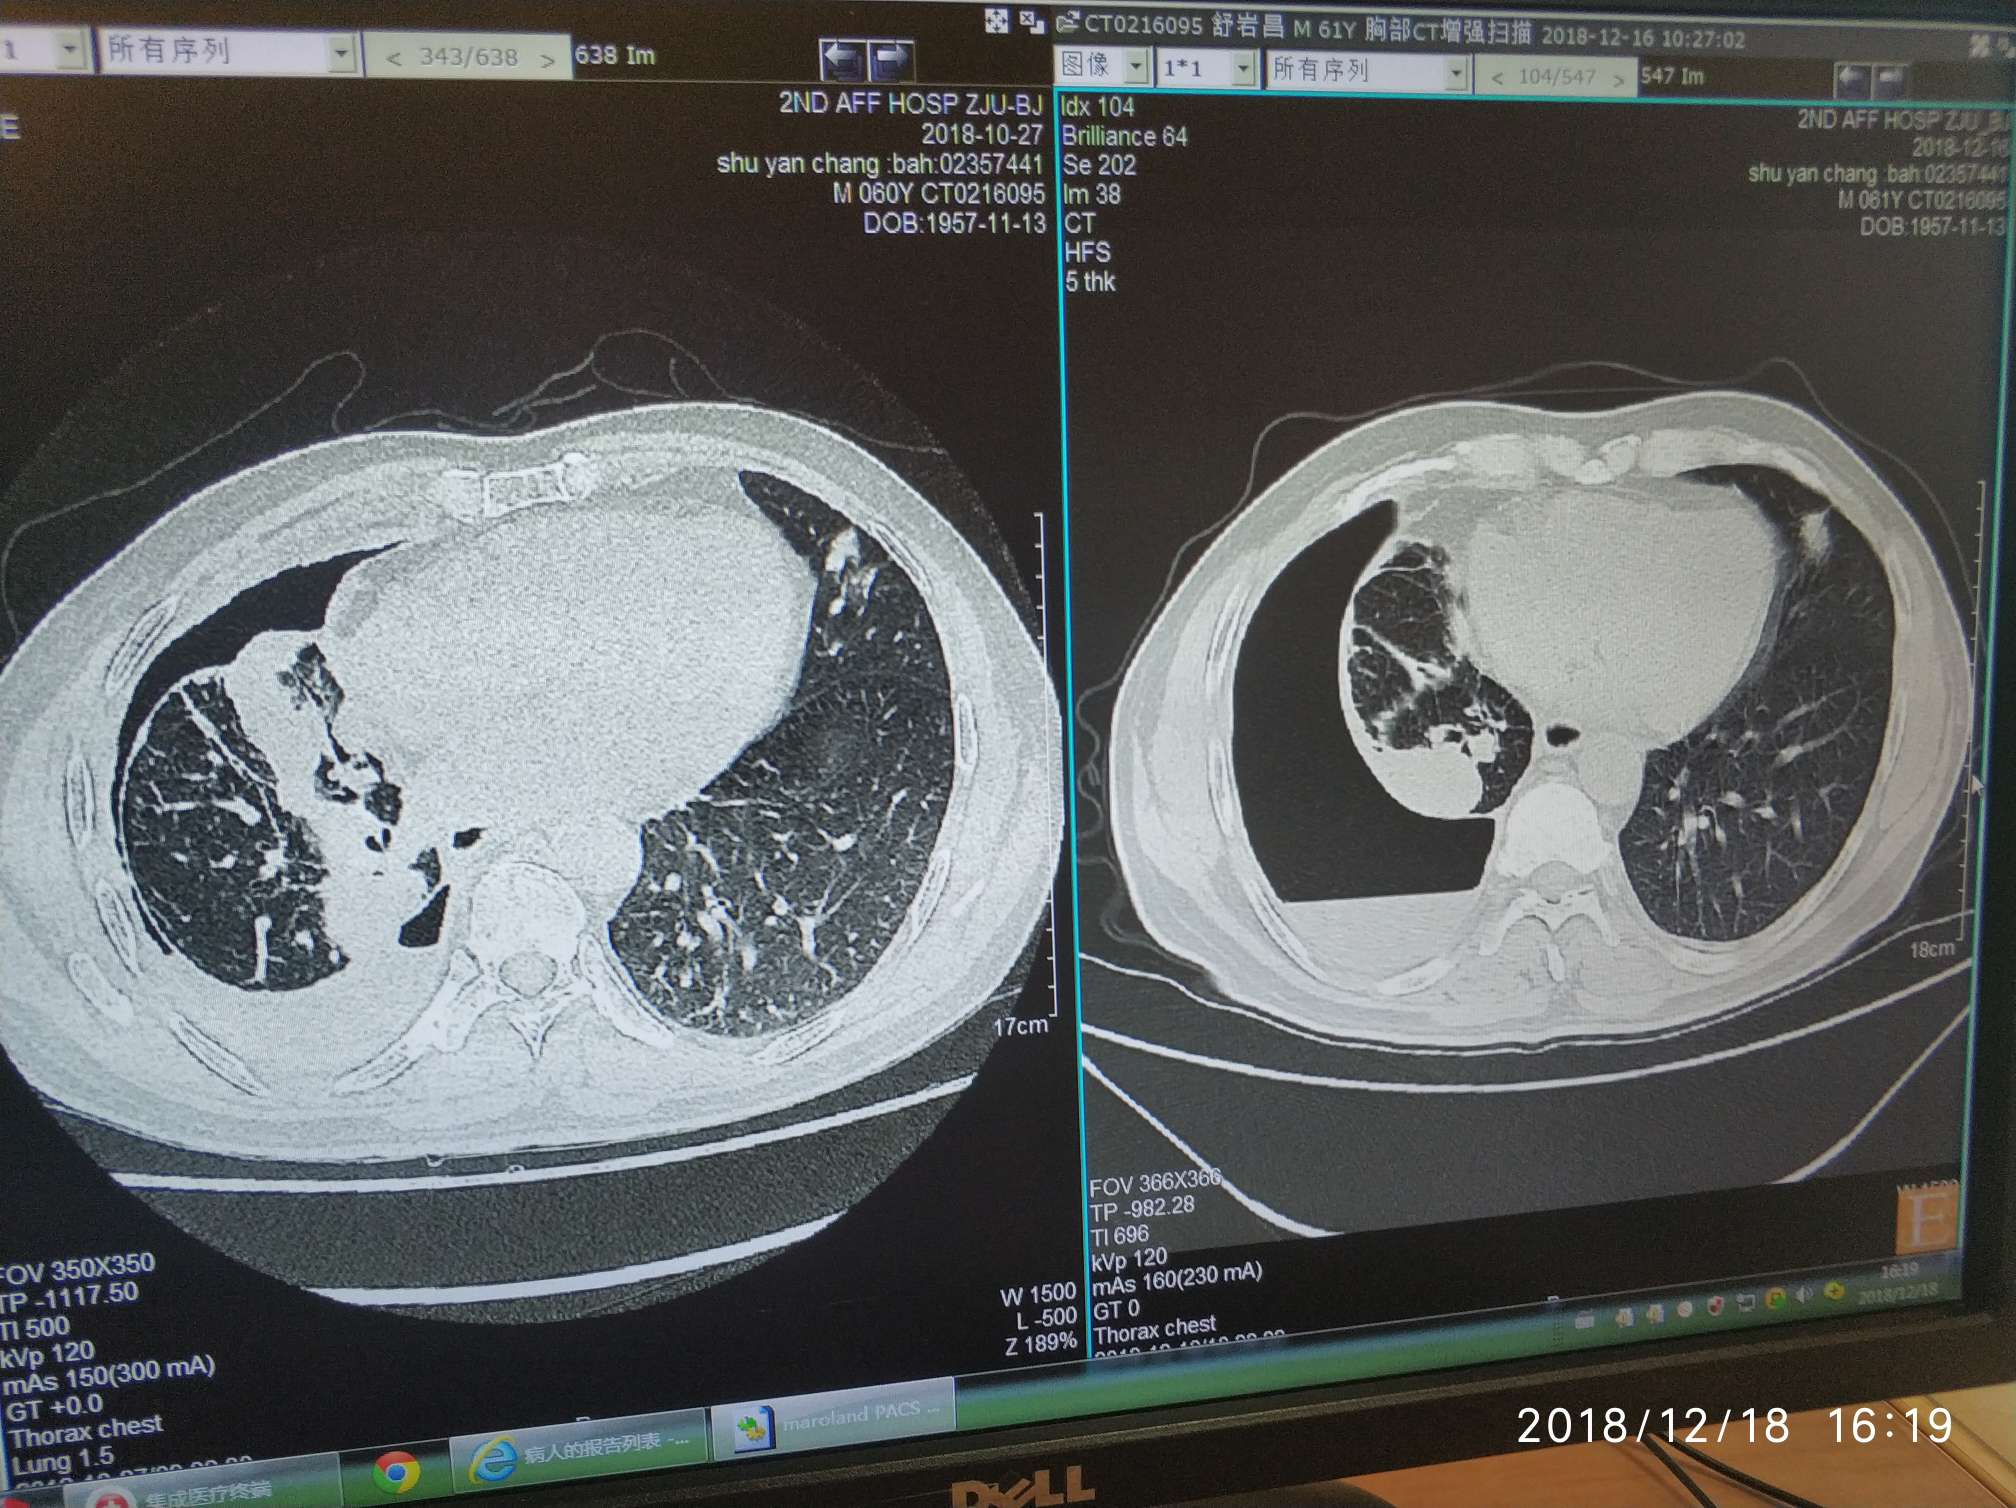

EGFR19突变,吃了易瑞沙快4个月,吃到2个月时候复查ct出现进展,医生建议易瑞沙联合化疗(卡铂+培美曲塞)这次来浙二第三次化疗ct显示病灶和淋巴结缩小,但是胸椎5磁共振怀疑骨转移需要换靶向药9291吗(外周血T790阴性)?还是局部放疗?头颅磁共振是好的,肝内有个囊肿怎么办?穿刺抽积气效果不好图片